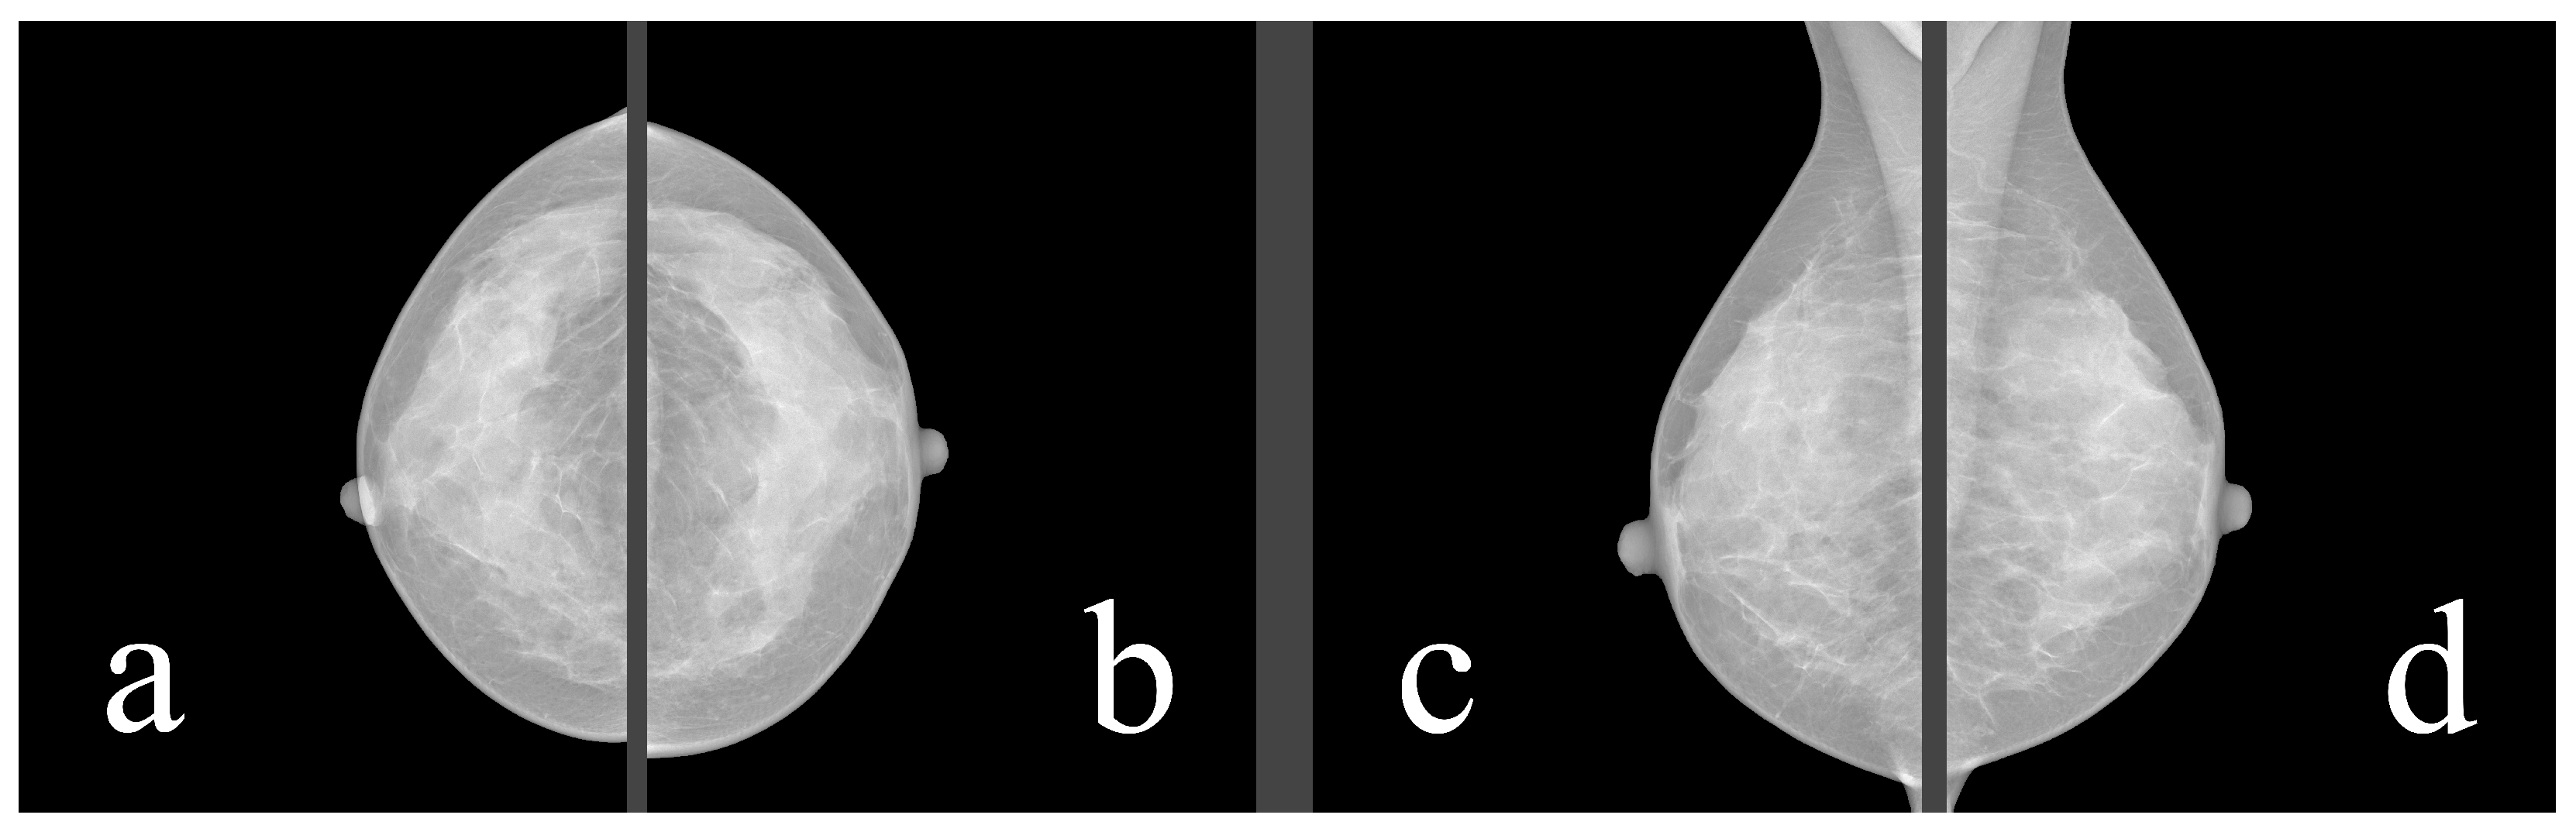

Mammography databases can offer various types of information. To better understand this information, it is valuable to understand the image examination process of a radiologist. The standard mammographic examination consists of four images, two projections for each breast: the craniocaudal (CC) view, which is a top-to-bottom view, and the mediolateral oblique (MLO) view, which is an oblique view (Figure 1). The ACR BI-RADS Atlas 2013 [10] was designed to standardize breast imaging reporting (Figure 2).

Figure 1. Four standard views: (a) right CC, (b) left CC, (c) right MLO, (d) left MLO. Source: [11].